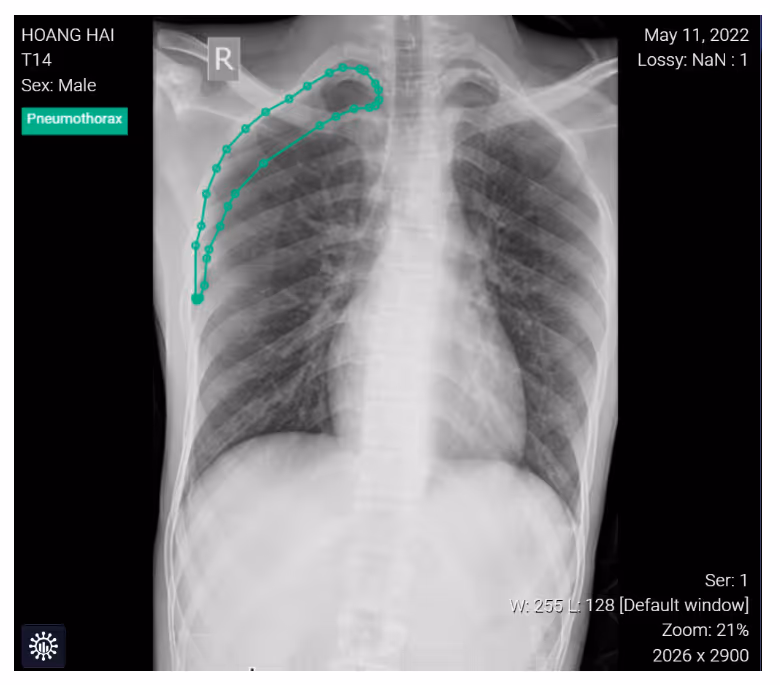

- A frontal chest radiographic image highlights the classic appearance of right-sided pneumothorax with a readily apparent visceral pleural line as seen without distal lung markings

ConclusionPhysicians can use DrAid for re-checking diagnostic results, thereby supporting the quality and efficiency of doctor performance.Interested in deploying DrAid at your health facility?Contact the Ferrum Health team to learn more.